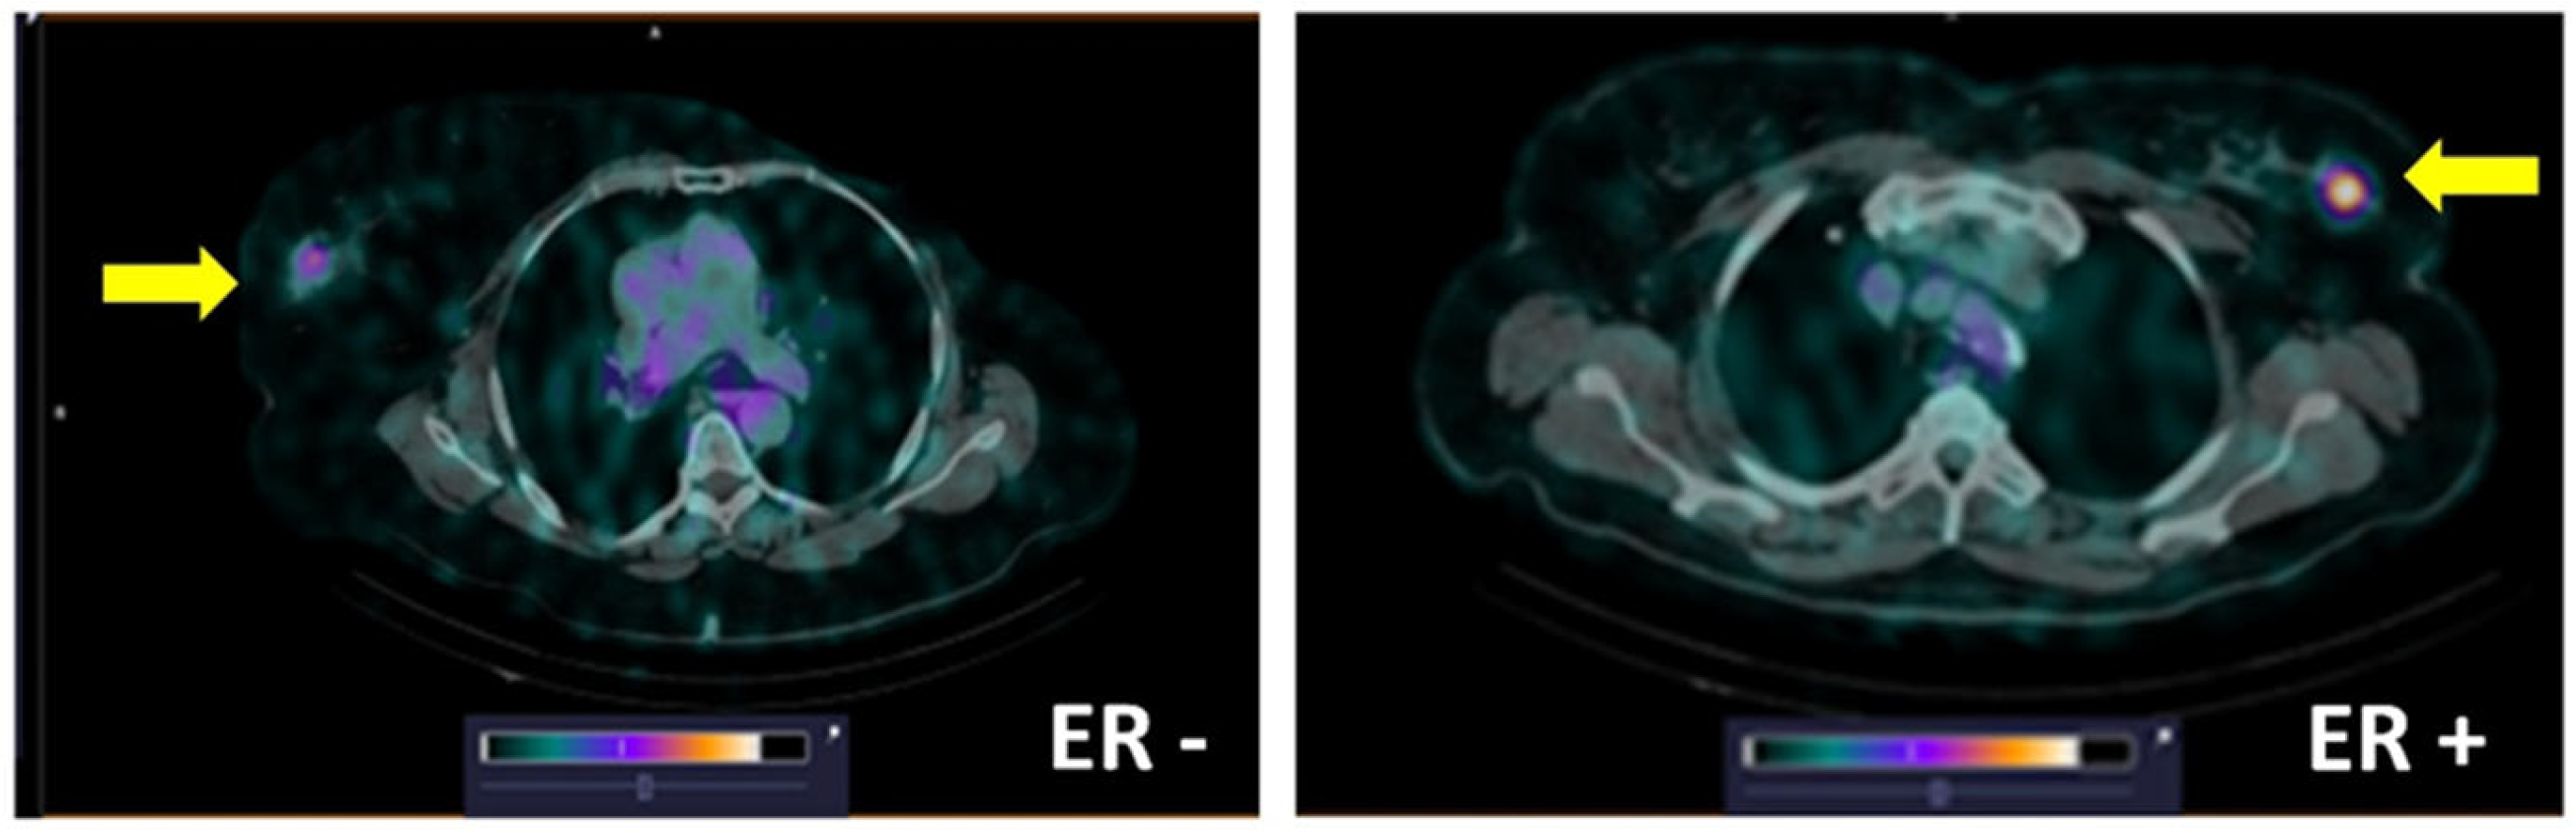

3. Results